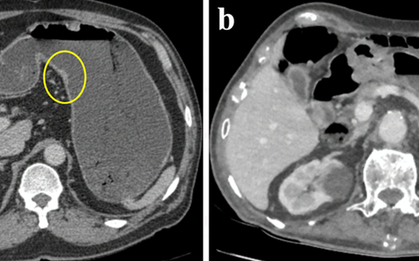

Đi khám vì khó tiêu bất ngờ phát hiện ung thư dạ dày

Bệnh nhân nam, 67 tuổi, ngụ TP.HCM cảm thấy mệt mỏi, đầy bụng khó tiêu nên đến bệnh viện khám và được chẩn đoán ung thư dạ dày. -